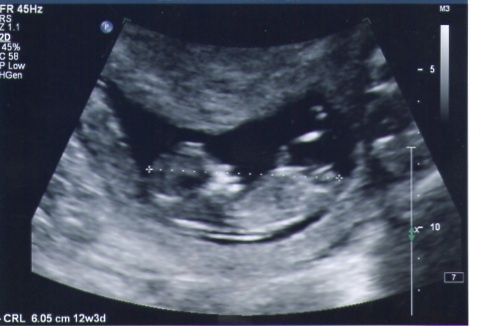

Baby was un cooperative and had legs crossed so this was the best pic I got. I am thinking that maybe the leg is in the way.

Does anyone have an idea as to what this little one may be???